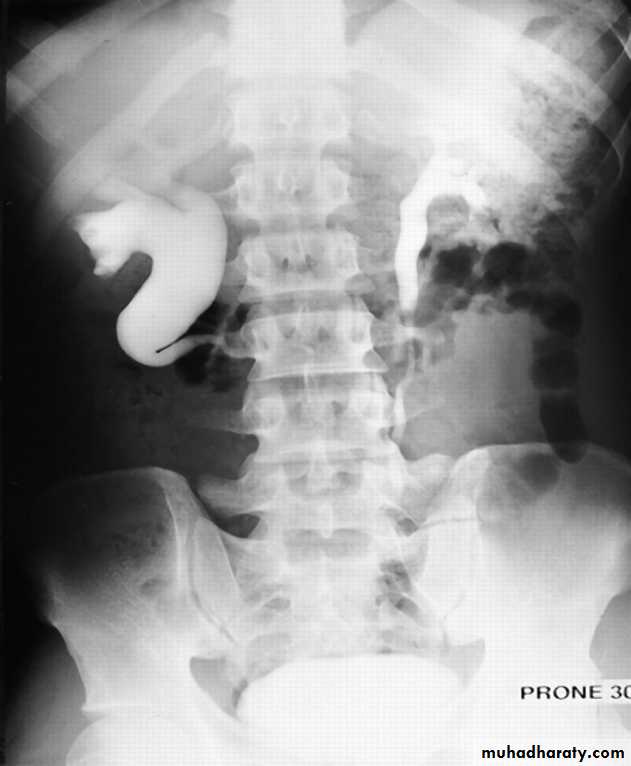

Horse shoe kidney -Kidneys may fail to separate.

-Almost invariably the lower poles remain fused.

-The kidneys axes are more parallel to the spine and malrotated.

-Diagnosis can be made by plain x-ray in some cases.

IVU shows

1. The kidneys at low position .

2.Close to the spine with long axis parallel to the spine .

3. Malrotation manifested by medially directed calyces.

4- The renal pelvis and ureters are anterior and lateral in position .